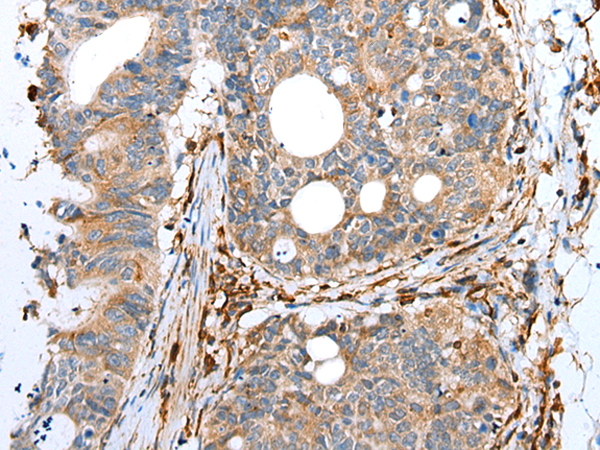

IHC positive control: |

Human gastric cancer and human lung cancer |

IHC Recommend dilution: |

25-100 |